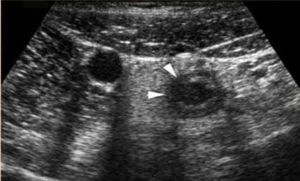

Acute appendicitis is one of the most common surgical pictures. In this image a perforated appendage is observed. Pointed with white arrows you can see how the wall of the appendix is irregular. A sign of appendicular perforation. You can read more of Acpendicits Acuda here: https://cerebromedico.com/cirugia/apendicitis-aguda